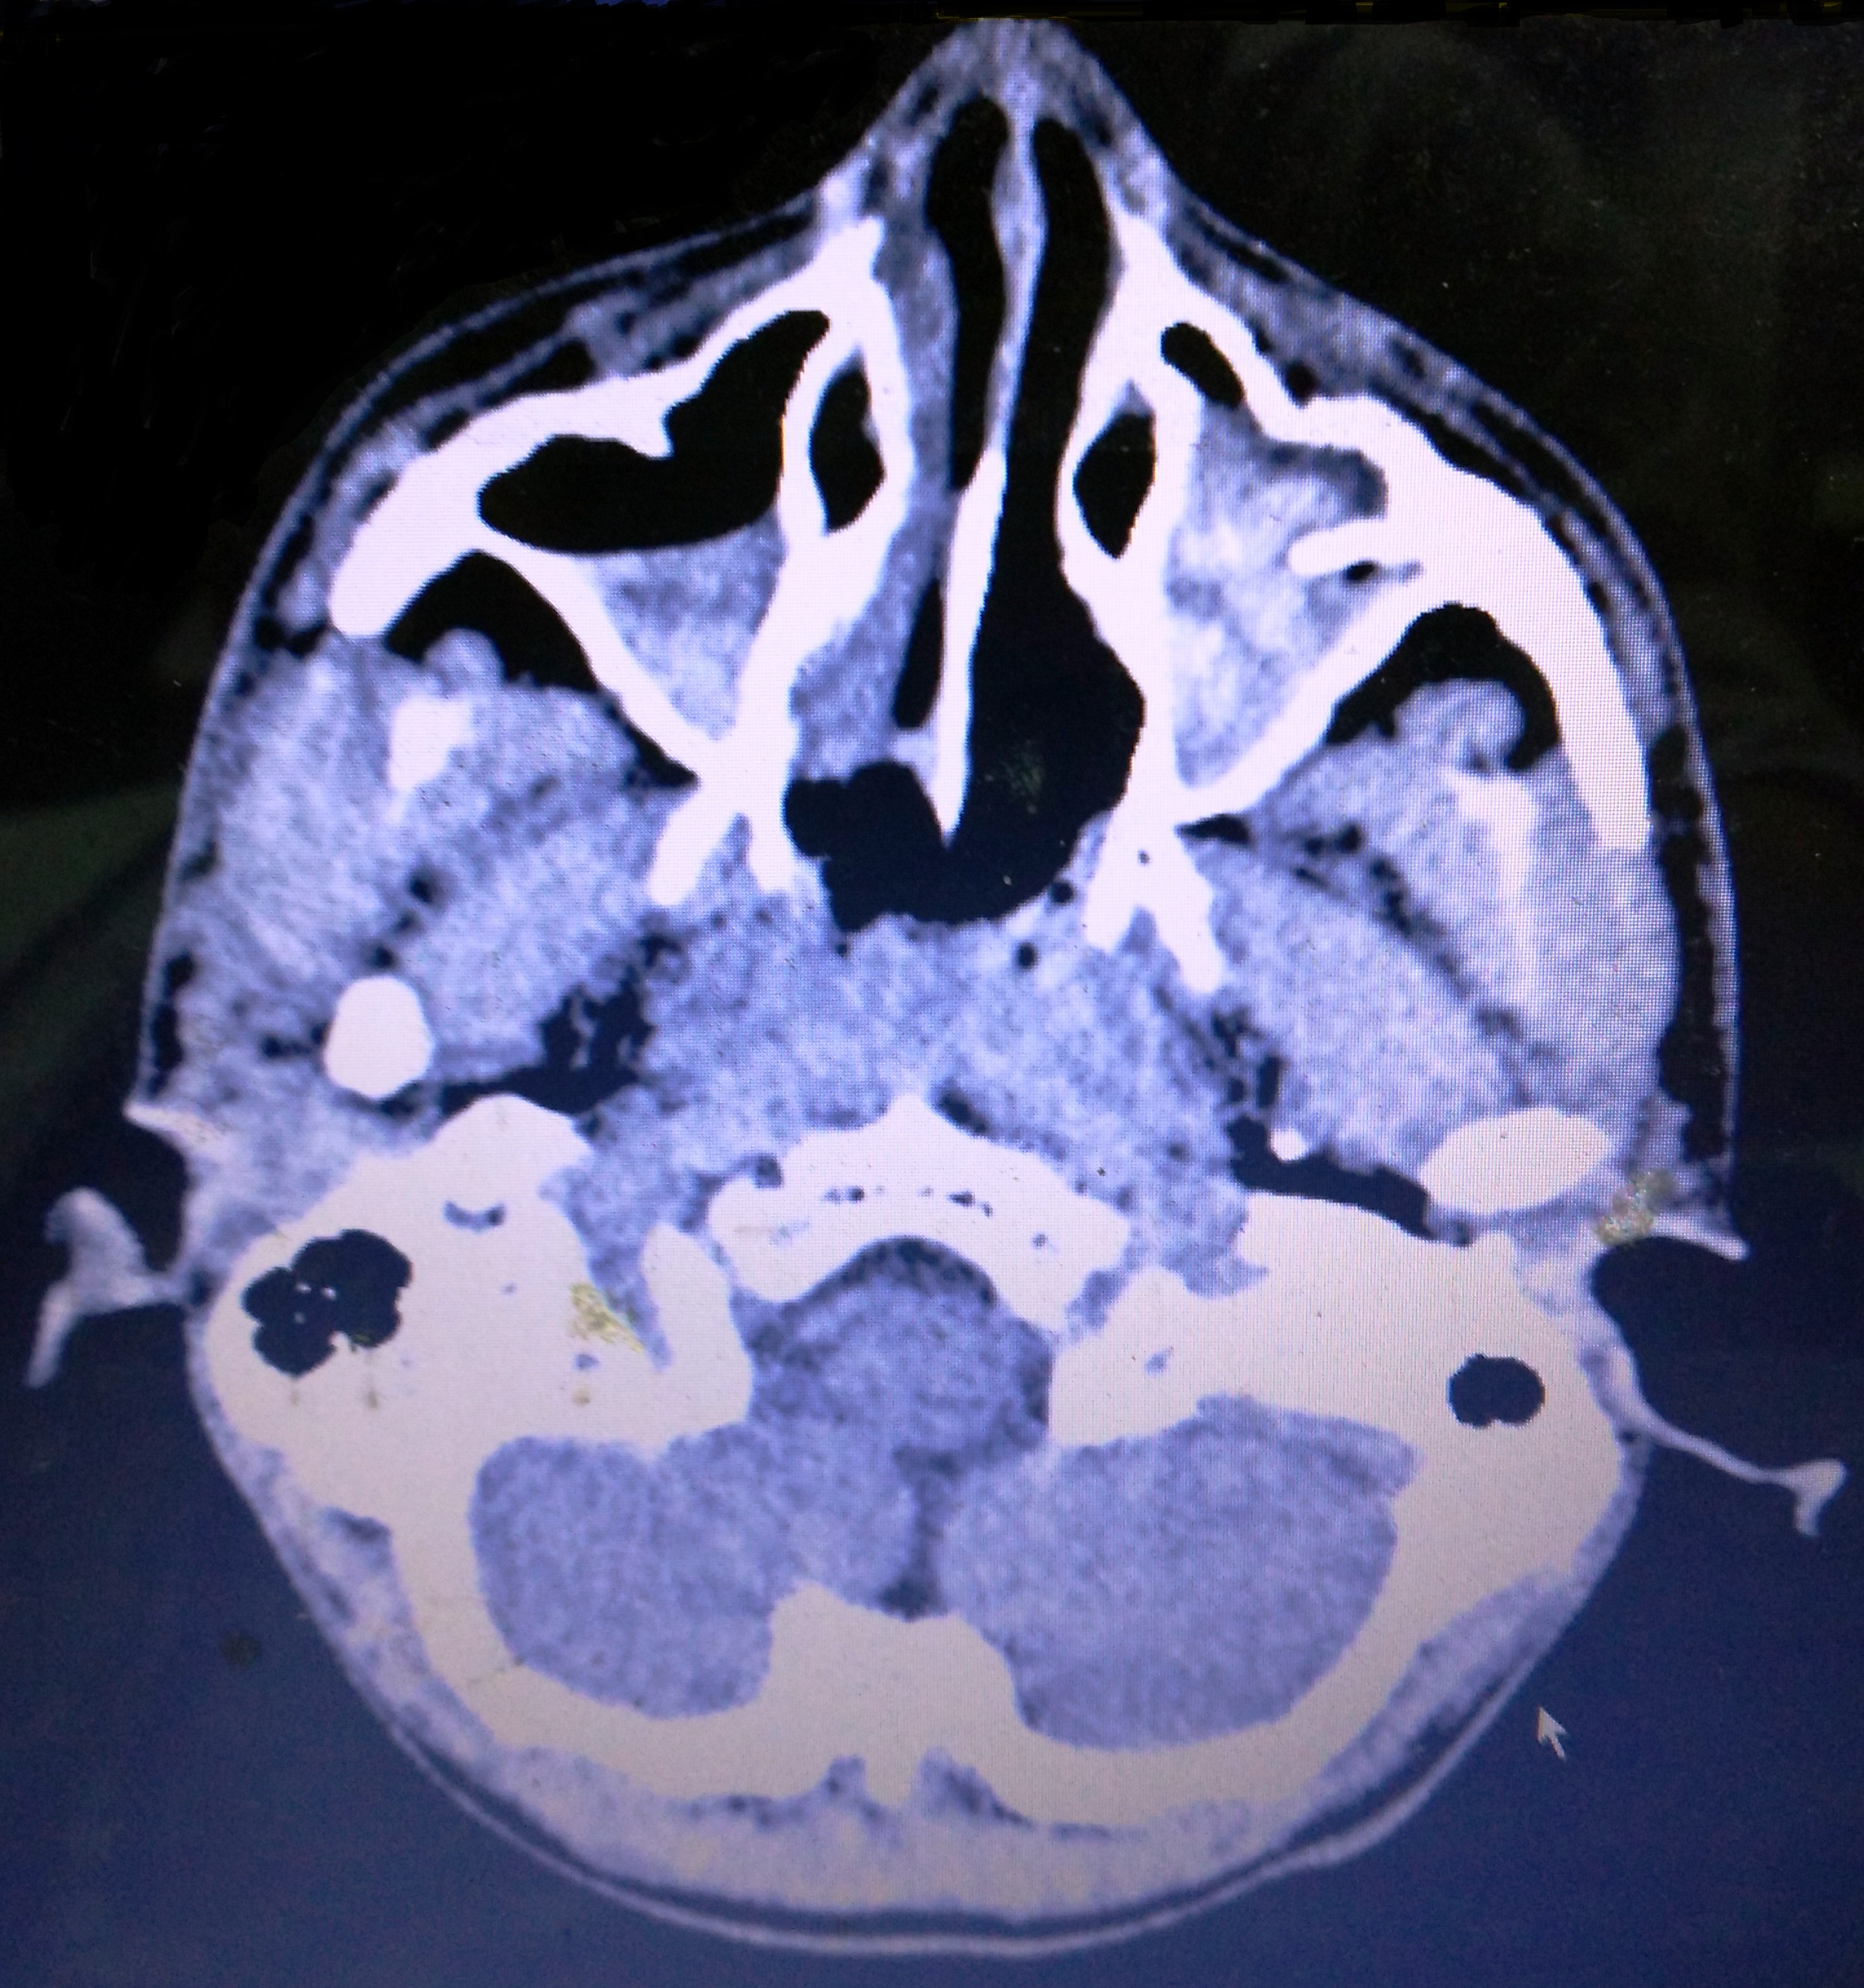

위턱굴은 인체에서 가장 큰 공기 부비동으로, 위턱뼈 몸통 내부에 위치하며, 부피는 약 10ml 정도이다. 위턱굴은 피라미드 모양으로, 세 개의 함요부를 가지며, 벽은 여러 뼈와 연골로 구성된다. 위턱굴은 상악 신경의 가지인 앞, 중간, 뒤 상치조 신경으로부터 감각 신경 지배를 받으며, 주변 구조로는 눈확, 날개입천장오목, 관자아래오목 등이 있다. 위턱굴의 크기는 개인에 따라 다르며, 사춘기 이후 빠르게 성장한다. 임상적으로는 상악동염, 구강-상악동 교통, 상악동암 등과 관련되며, 나이가 들면서 위턱굴이 커지는 특징을 보인다. 위턱굴은 레오나르도 다 빈치에 의해 처음 발견되었고, 나다니엘 하이모어에 의해 상세히 묘사되었다.

위턱굴은 인체에서 가장 큰 부비동이다.[1][4] 평균 부피는 약 10ml이다.[1] 이는 위턱뼈 몸통 안에 위치하며,[1][4][3] 크기가 클 경우 관골 및 이틀 돌기로 확장될 수 있다. 피라미드 모양이며, 꼭지점은 위턱뼈의 관골 돌기를 향하고 바닥은 코의 가쪽 벽에 해당한다.[3]

천장은 안와(눈구멍)의 바닥에 의해 형성된다. 이곳으로는 안와하 신경과 안와하 혈관이 지나간다.

2. 2. 특징

위턱굴의 벽에는 몇 가지 중요한 구조물이 지나가면서 능선을 형성한다. 위턱굴의 위쪽 벽(지붕)과 앞쪽 벽이 만나는 부분에는 하안와 신경관이 지나가면서 만들어진 능선이 관찰된다. 또한, 위턱굴의 뒤쪽 벽에서는 치조관에 의해 형성된 능선이 나타나기도 한다. 이 신경관과 치조관은 신경과 혈관이 지나가는 통로 역할을 한다.2. 3. 신경 분포

위턱굴(상악동)은 섬모가 누공 방향으로 움직이는 점막골막으로 덮여 있다. 이 막 내벽은 또한 슈나이더 막이라고도 하며, 이는 조직학적으로 내측(또는 해면) 면에는 가성 중층 원주 상피 세포가 있고 골막은 골 조직 면에 있는 이층막이다. 상악동의 크기는 다른 두개골에서, 심지어 동일한 두개골의 양쪽에서도 다르다.[4]2. 5. 주변 구조와의 관계

위턱굴의 천장은 또한 눈확의 바닥이기도 하다. 위턱굴과 그 벽 뒤쪽에는 날개입천장오목과 관자아래오목이 있다.2. 6. 변이

상악동 부비동염은 위턱굴, 즉 상악동에 생긴 염증을 말한다. 부비동염의 주요 증상으로는 염증이 생긴 부위 근처의 두통, 불쾌한 냄새가 나는 코나 목 분비물, 발열, 전신 쇠약감 등이 나타날 수 있다. 염증이 있는 부위의 피부는 만지면 아프거나(압통), 열감이 느껴지거나, 붉어지기도 한다. 방사선 사진을 찍어보면 정상적으로 공기가 차 있어 검게 보여야 할 상악동이 염증으로 인한 점액 저류 때문에 불투명하게 보이거나 뿌옇게 나타난다.[7]